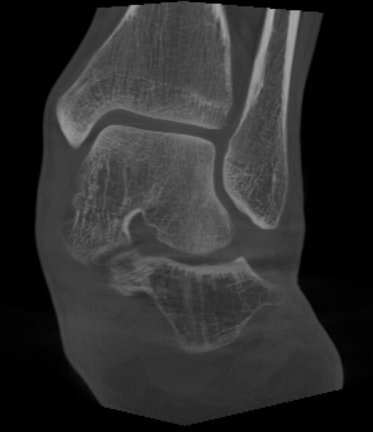

Tuttavia, oggi, la TAC in carico, come accennato sopra, è un esame fondamentale per diagnosticare un piede piatto che evolve e peggiora.

Si tratta di uno studio TAC eseguito con una tecnologia che permette di acquisire l’esame in piedi.

Permette, infatti, di andare ad osservare parametri aggiuntivi:

- Faccetta sottoastragalica anteriore: l’articolazione sottoastragalica (articolazione tra calcagno e astragalo) è infatti costituita da due componenti articolari (in alcune sue varianti anatomiche addirittura da 3). Lo studio specifico della sottoastragalica anteriore in carico è un potente indice di predittività dell’evoluzione del piede piatto patologico. Ci dice se dobbiamo agire e con quanta fretta.

- Impingement sinus tarsi: indica se l’articolazione sottoastragalica è diventata pienamente artrosica e quindi deve essere riallineata con il suo sacrificio (artrodesi sottoastragalica) o se il piede piatto può essere ricostruito preservando ogni sua funzione e movimento. E’ il motivo per cui in alcuni casi è importante scegliere il momento giusto in cui operarsi: non arrivare troppo presto, ma neanche troppo tardi.

Tac in carico di un piede piatto pre-intervento con assi di riferimento per le deformità.